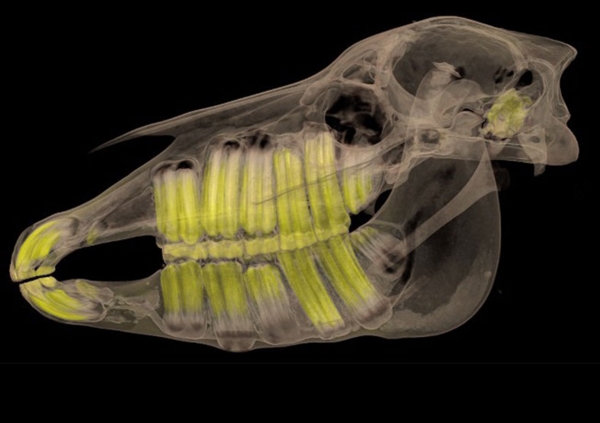

在随后的幻灯片中,您将看到来自瑞典医学图像科学与可视化中心(the Center for Medical ImageScience and Visualization ,CMIV)的Anders Persson和他的同事们运用CT,MRI和超声得到的令人惊叹的尸检图片。这些图片描绘了人体骨骼,消化道,循环系统和大脑以及野猪的前端结构。

2,动物,头部;骨骼完整性清晰可见,特意用不同的颜色强调了牙齿。